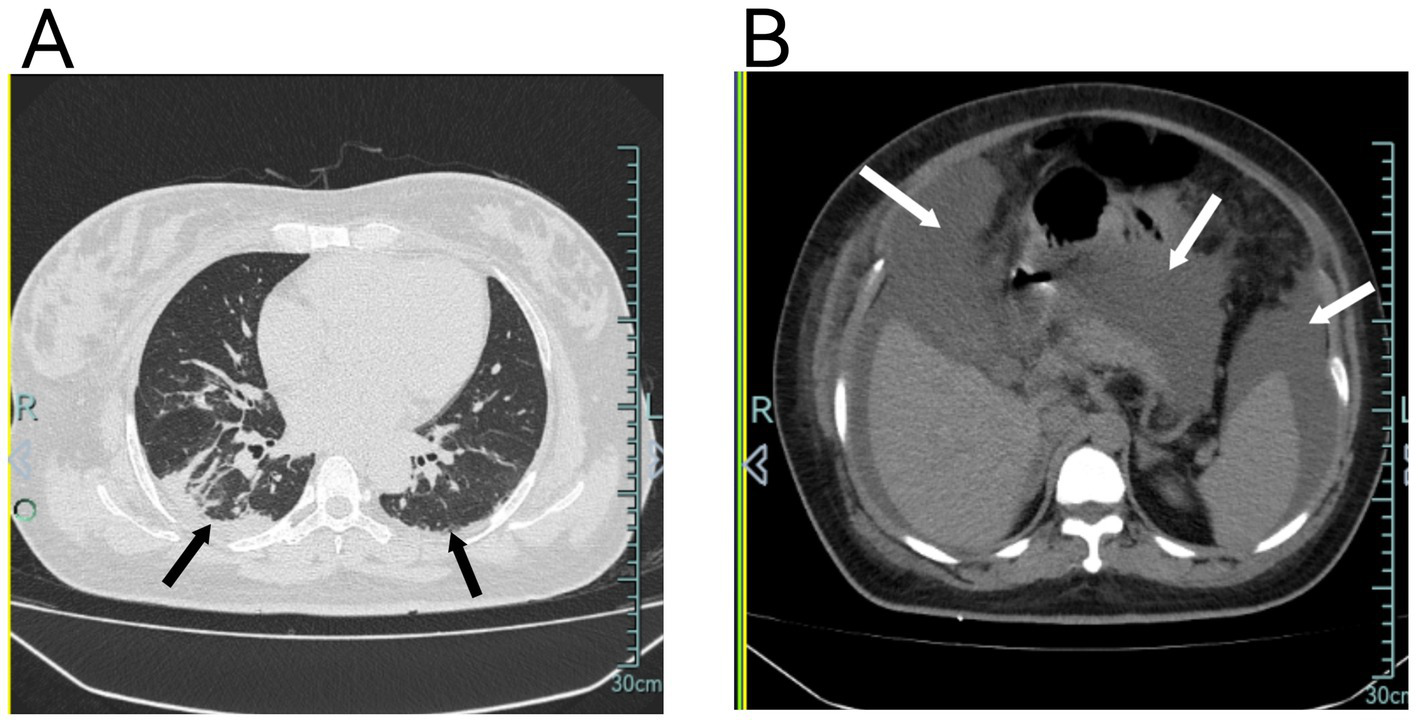

Figure 2

(A) Chest CT shows diffuse pulmonary exudates in both lungs, partial atelectasis in the right lower lobe, and minimal pleural effusion bilaterally. (B) Chest CT also demonstrates significant abdominal fluid accumulation.